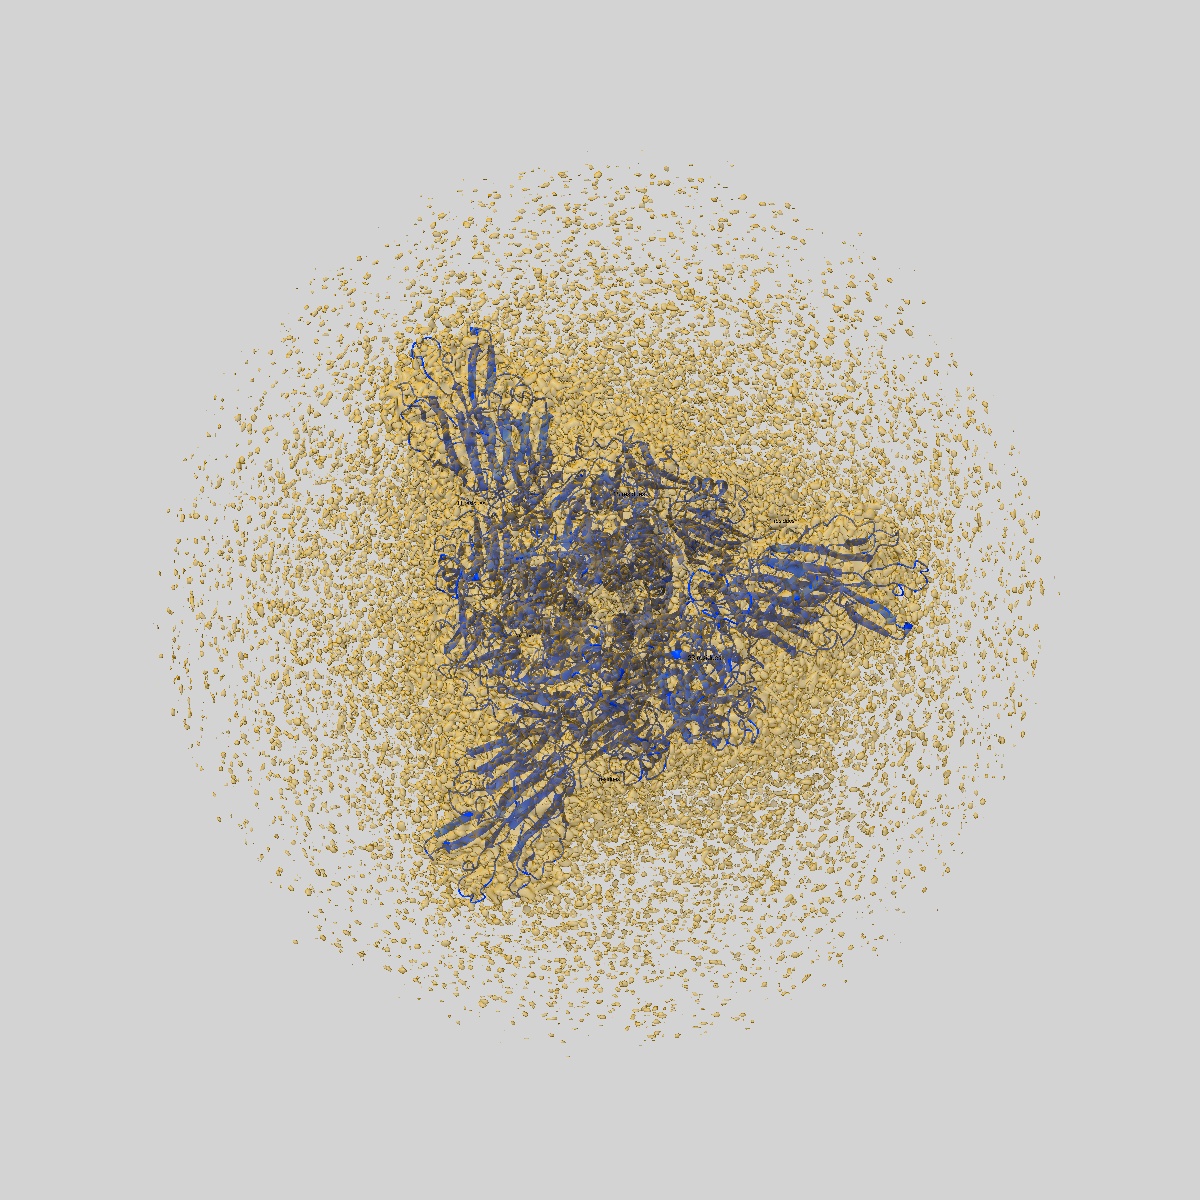

JN.1 SARS-COV-2 Spike 1-up conformation

Sample: S protein trimer

Fitted models: 9d8i

SARS-CoV-2 JN.1 and KP.2 spike characteristics and neutralization of JN.1-derived sublineages and T cell responses from mice immunized with monovalent JN.1- and KP.2-adapted BNT162b2 COVID-19 vaccines